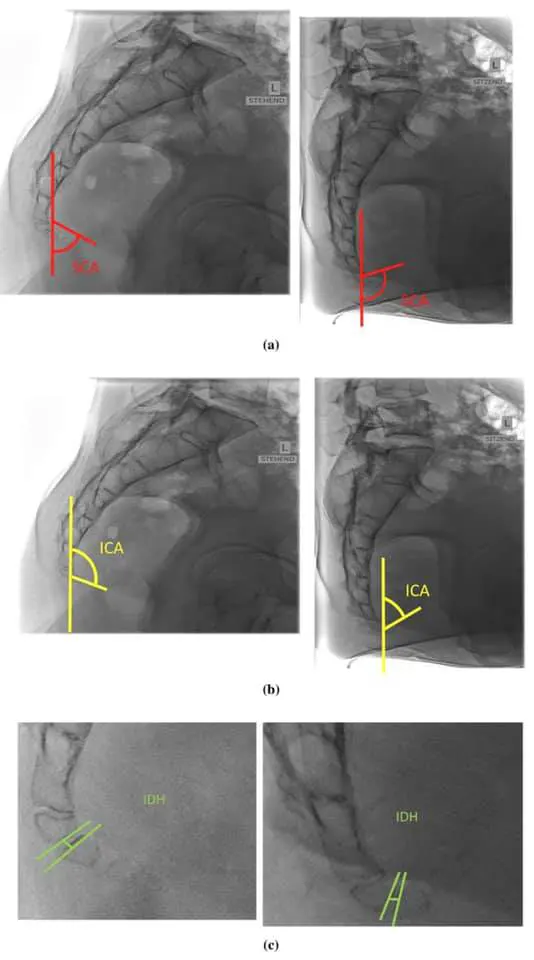

Рентгеновские снимки пациентов с кокцигодинией в положении стоя и сидя.